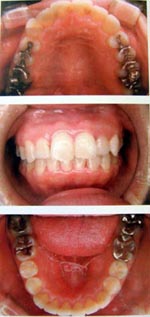

成人の場合・1日10時間装着

顎が小さく症状がある方には有効です。